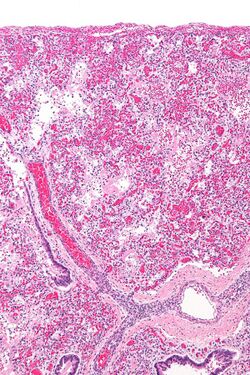

Micrograph of diffuse alveolar damage, the histologic correlate of ARDS. H&E stain.

ARDS is a form of fluid accumulation in the lungs not explained by heart failure (noncardiogenic pulmonary edema). It is typically provoked by an acute injury to the lungs that results in flooding of the lungs' microscopic air sacs responsible for the exchange of gases such as oxygen and carbon dioxide with capillaries in the lungs.[12] Additional common findings in ARDS include partial collapse of the lungs (atelectasis) and low levels of oxygen in the blood (hypoxemia). The clinical syndrome is associated with pathological findings including pneumonia, eosinophilic pneumonia, cryptogenic organizing pneumonia, acute fibrinous organizing pneumonia, and diffuse alveolar damage (DAD). Of these, the pathology most commonly associated with ARDS is DAD, which is characterized by a diffuse inflammation of lung tissue. The triggering insult to the tissue usually results in an initial release of chemical signals and other inflammatory mediators secreted by local epithelial and endothelial cells.[citation needed]

Neutrophils and some T-lymphocytes quickly migrate into the inflamed lung tissue and contribute in the amplification of the phenomenon. The typical histological presentation involves diffuse alveolar damage and hyaline membrane formation in alveolar walls. Although the triggering mechanisms are not completely understood, recent research has examined the role of inflammation and mechanical stress.[citation needed]